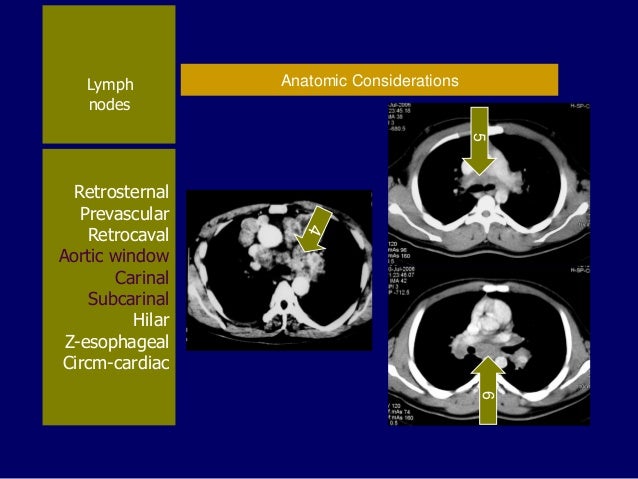

lymphadenopathy lymph nodes retrosternal subcarinal carinal

Lymph nodes thoracic radiology. A brief guide to cancer imaging. Thoracic lymph node stations radiopaedia